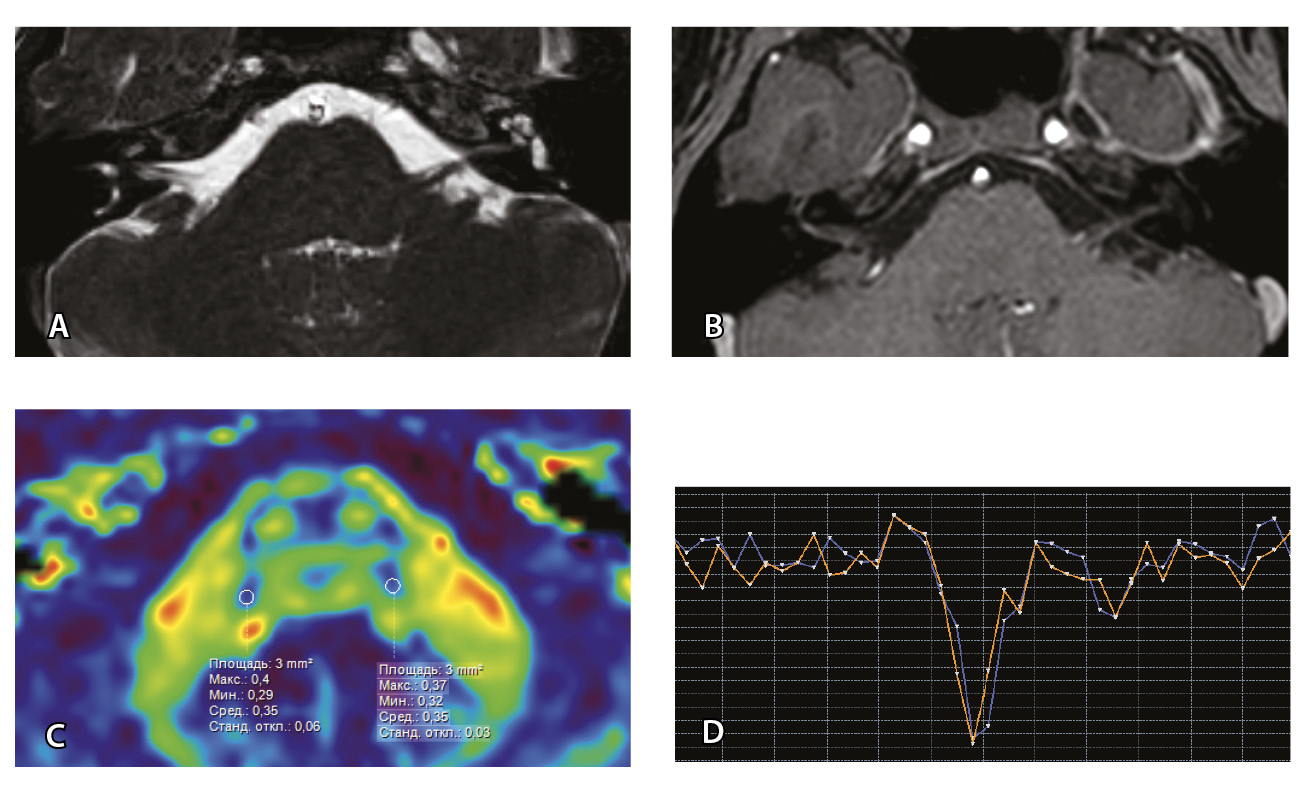

Для наглядности представляем МП-МРТ ребенка без выявленных патологических изменений со стороны черепно-мозговых нервов согласно клиническим данным и при МП-МРТ (рис. 3) Исследование с контрастированием у ребенка без НЛН проводилось по другим показаниям для исключения острого демиелинизирующего процесса.

Рис. 3. Пациент Г. Магнитно-резонансная томография (МРТ) головного мозга: А – прицельная T2-SSFP на область мосто-мозжечкового угла; Б – Т1-взвешенное изображение с контрастным усилением; В – диффузионно-тензорная МРТ (фракционная анизотропия); Г – Т2*-перфузия (здесь и далее графики перфузии отражают зависимость повышения интенсивности МР-сигнала, то есть накопления контрастного вещества (вертикальная ось) от времени (горизонтальная ось), тем самым иллюстрируя основные показатели перфузии – relCBV, TTP, MTT). На изображениях T2-SSFP патологические изменения на уровне прохождения лицевых нервов во внутренних слуховых проходах (А), повышенное накопление вещества корешками лицевых нервов (Б) не определяются. Показатели фракционной анизотропии (В) и Т2*-перфузии (Г) на уровне моторных ядер лицевых нервов симметричны